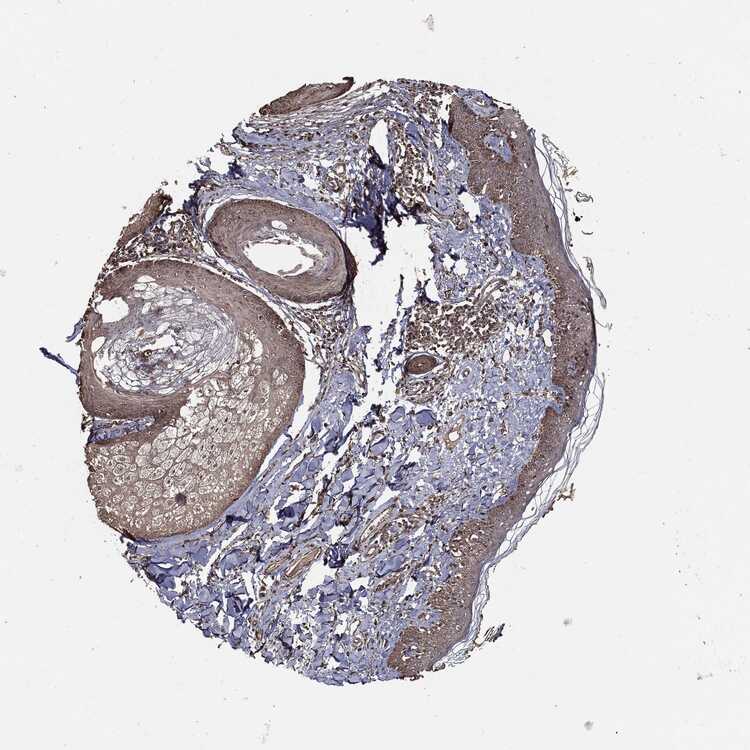

SKIN 1 - Antibody stainingi

Antibody staining in the annotated cell types in the current human tissue is reported as not detected, low, medium, or high, based on conventional immunohistochemistry profiling in selected tissues. This score is based on the combination of the staining intensity and fraction of stained cells.

Each image is clickable and will lead to virtual microscopy that enables deeper exploration of all samples and also displays staining intensity scores, fraction scores and subcellular localization as well as patient and tissue information for each sample.

Antibody CAB069425Antibody CAB080053Antibody CAB080065Antibody CAB080070Antibody CAB080081Antibody CAB080095Antibody CAB080097

Langerhans Not detectedNot detectedMediumNot detectedNot detectedNot detectedNot detected

Fibroblasts Not detectedNot detectedMediumMediumNot detectedMediumNot detected

Keratinocytes MediumMediumLowNot detectedNot detectedLowNot detected

Melanocytes Not detectedHighNot detectedMediumNot detectedMediumMedium